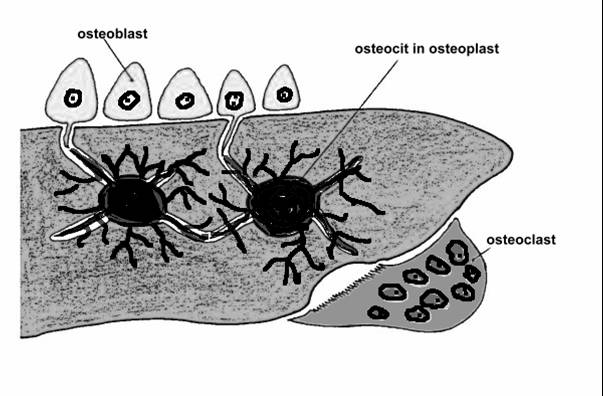

TESUTUL OSOS SI OSTEOGENEZA

TESUTUL OSOS SI OSTEOGENEZA PREPARATE DE DESENAT Osteon, os slefuit Os spongios, col. HE Osificare encondrala PREPARATE DEMONSTRATIVE 1. &nbsCiteste tot ... 988 cuvinte

Dimensiune mica

+ cu imagini |